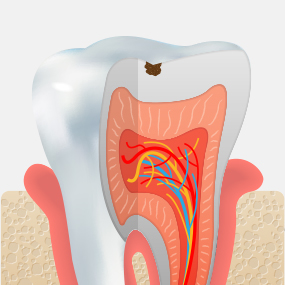

충치는 스스로 회복되지 않기 때문에,

정기적인 검진과 조기 치료가 건강한 치아를 오래 보존하는 가장 좋은 방법입니다.